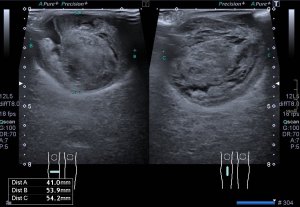

Finalmente, imagen 5 y 6 que te enseñan el tratamiento aplicado a las gonadales de forma bilateral, embolizadas con material hiperecogénico en su interior que en la reconstrucción coronal del CT se objetiva como una imagen bilateral brillante lateral a los grandes vasos.